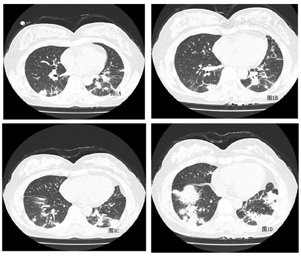

实验室检查:血气分析(FiO2:37%)pH 7.464 ,PaO2:87.4 mmHg (氧合指数:236),血常规:白细胞2.40×109/L,中性粒细胞占:50.5%;淋巴细胞占:23.8%。血红蛋白98 g/L,血小板180×109/L;血沉:81mm/h;血清铁蛋白:1964ng/mL,抗核抗体1:100,胞浆颗粒型,肌炎谱:抗MDA5-IgG(++)、抗Ro52-IgG (+++);胸部HRCT示:双下肺分布实变影,伴有肺容积缩小(图3)。

甲泼尼龙500mg×3天,继以逐渐减量(250mg×3天、160mg×3天、80mg×5天);环孢素75mg,bid;环磷酰胺0.8g qw×3次,余予以全覆盖抗感染以及吡非尼酮600mg tid /d抗纤维化治疗。患者于11月21日诉左侧大腿肿痛。血常规:血红蛋白:65g/L;血小板:89×109/L。凝血功能PT14.4秒、APTT42.1秒、纤维蛋白原1.24g/L。不能排除下肢肌间出血可能,急行床边B超:左大腿软组织区包块--血肿?行下肢动脉CT:考虑左侧大腿肌间血肿形成(图5)。介入科会诊后行超选择性左侧股深动脉-穿动脉栓塞术(图6)。患者出血停止,血肿吸收,好转出院。目前仍在随访中。